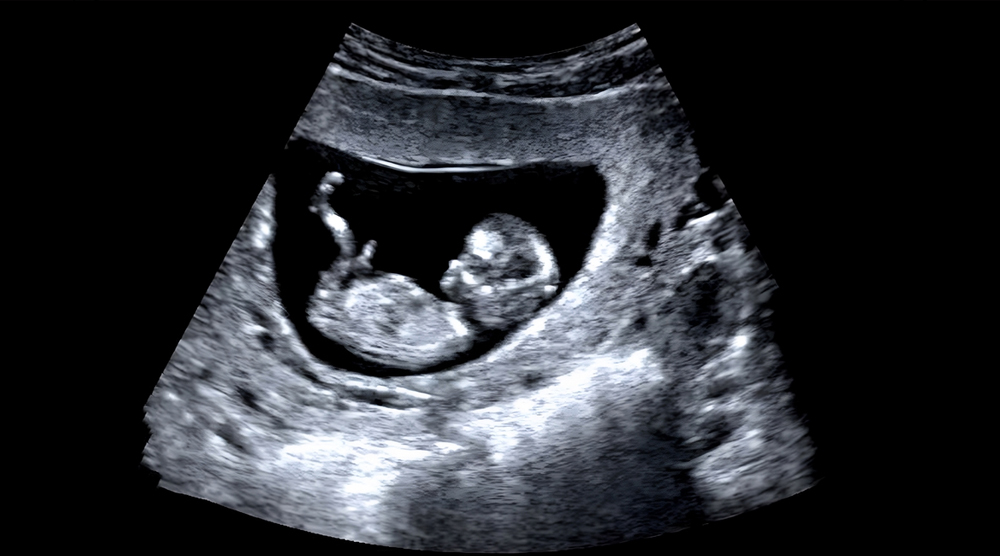

- Obstetric Ultrasound

Antenatal (Pregnancy) Care

Comprehensive checkups, scans, nutritional support & counseling throughout your pregnancy.

Ultrasound, Doppler, and routine scans with expert radiologist guidance.

Baby Pregnancy Timeline

Yes, we have in-house ultrasound and Doppler scanning facilities for pregnancy and gynecology-related assessments.